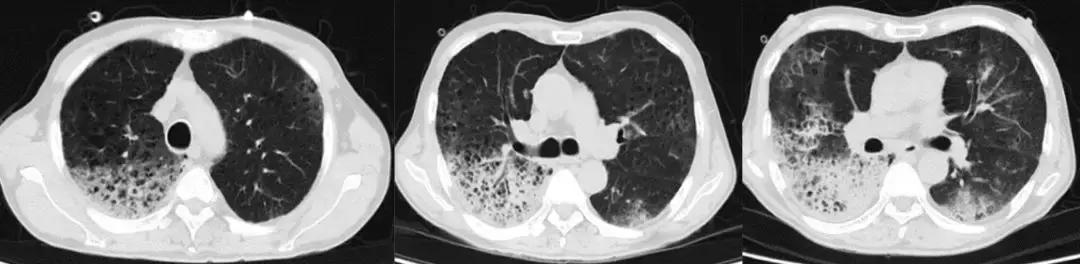

16岁,男,主因:发热1周,呼吸困难1天入院,既往臀部皮肤疖肿,输尿管结石,体外碎石术后,输尿管D-J管置入术后。泰能联合万古霉素治疗无效。

支气管镜结果:H7N9。仔细追问患者病史:仅仅有经过养鸡场。

经验教训

您能根据影像判断患者是病毒感染吗?但是在广谱抗生素抗感染治疗无效的ARDS患者,一定警惕病毒感染。